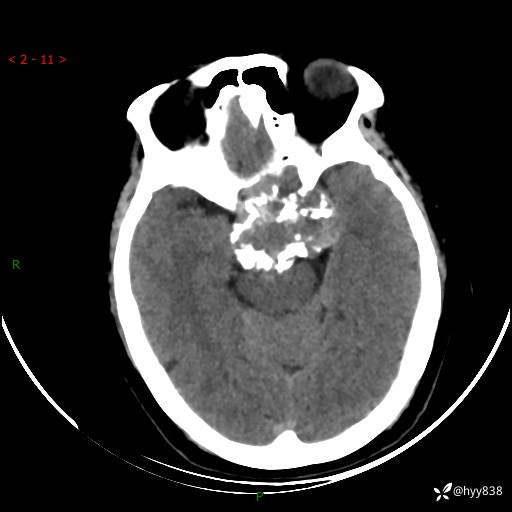

老年女性,视力下降3年。鞍区钙化性肿块,鉴别诊断有哪些---(有结果)

简要病史:患者3年前无明显诱因左眼出现视力下降,出现视物模糊,无头痛,无头晕,无恶心、呕吐,无意识障碍,无肢体麻木及抽搐,无心慌、胸闷,无腹痛、腹胀等不适,无旋地转感。个月前右眼视力下降,患者视物模糊逐渐下降,自诉看东西有雾感。在当地医院眼科就诊,症状无好转,行头部MR提示:鞍区肿物。现患者为求诊治来我科就诊,在当地市中医医院行头部CT:提示鞍区占位。患者现求进一步诊治来我院就诊,门诊以“鞍区肿物”收入我科。 患病以来,患者精神、饮食、睡眠尚欠佳,大小便如常,体力体重无明显变化。

临床诊断:鞍区肿物

颅脑CT平扫